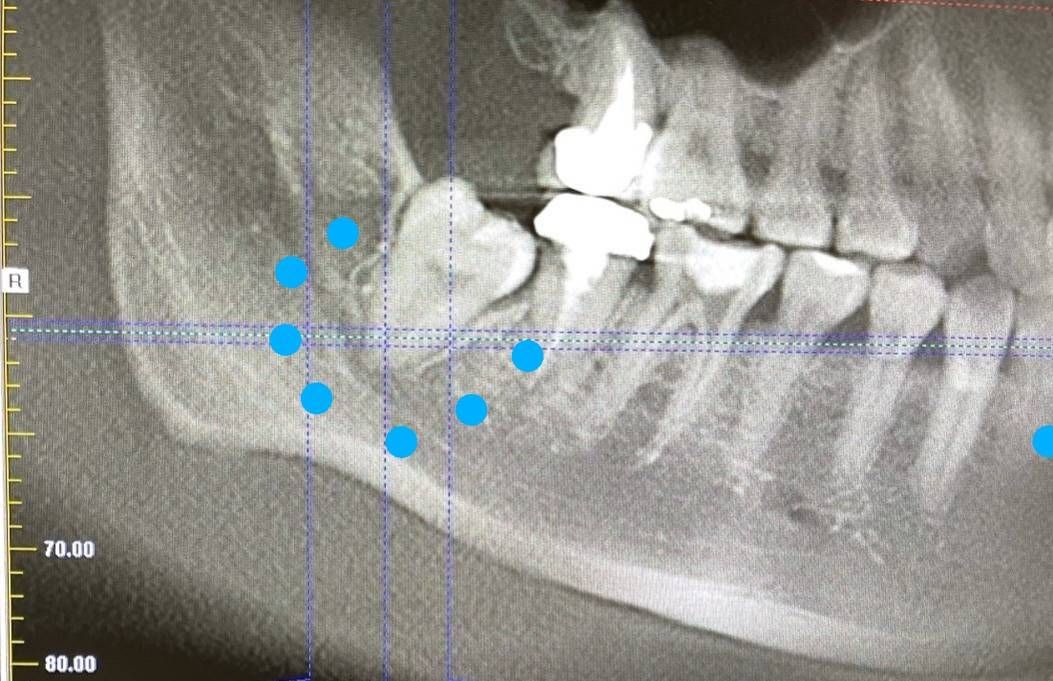

天主教聖保祿醫院牙科主任徐偉軒醫師指出,通常下巴臉頰麻痺及疼痛症狀,最困難是疾病鑑別診斷,容易先想到可能是顏面神經、三叉神經所引發的問題。病人沒先就醫神經內科而先看診牙科,主要是自我認定蛀牙引發牙疼及麻痺,但病人在治療蛀牙及發炎後,仍有疼痛及麻痺感,所以醫師安排電腦斷層檢查。

▲醫師以微創手術不影響下齒槽神經的方式,安全拔除右下智齒,讓王小姐下巴麻木情形改善很多。(圖/聖保祿醫院提供)